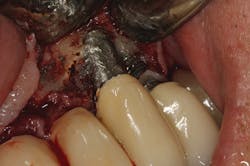

No. 2—Contamination from implant cement

Once again, the literature is replete with case reports and case series describing soft- and hard-tissue loss due to excess dental cement left at the time of implant crown insertion.8 In one study, 90% of the implant crowns inserted with cement exhibiting inflammation and bleeding upon probing were due to cement in the peri-implant sulcus.9 Cement acts as a nidus for bacteria and induces a rapid hard-tissue loss around the dental implant fixture (figures 2 and 3).